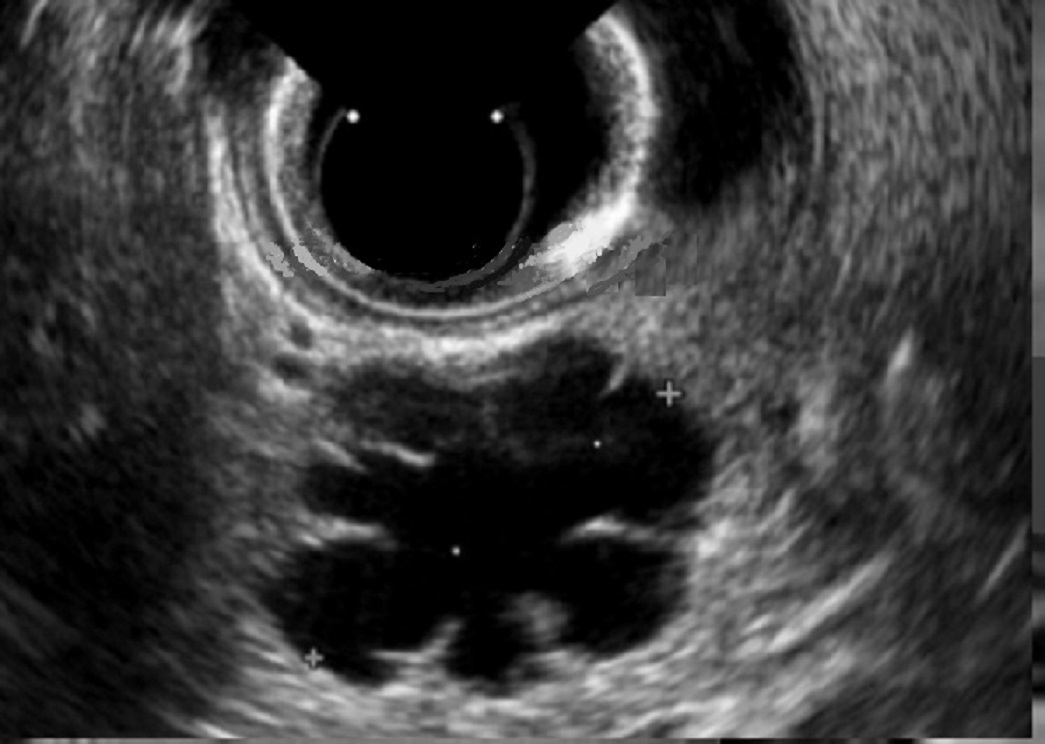

Echographie : Image

echographique d'une cystadenome sereuse est une masse

hypoechogene , contour nette , polylobe situe du corps ( 34%

) du queue ( 26% ) , sa contenue le plus souvant sous forme

de multiple microkyste aechogene , nids d'abeille ou eponge

, cicatrice fibreuse central et calcification central parfoi

se en voyant. Les oligokystes sont se

presenter souvant a la tete du pancreas (40/% ),

uniloculaire macrokystique seul . Endo

echographie et ponction exploratrice presenter sa liquide

est claire et pauvre

en enzymes pancréatiques, en ACE et Ca 19-9